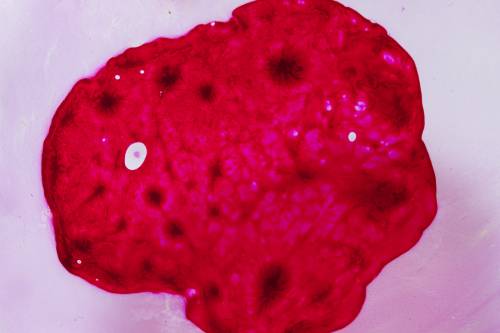

Tratamiento de poliposis endometrial

La histeroscopia (Entrar a través del interior del útero), permite quitar y eliminar pólipos endometriales de diferentes tamaños en las diferentes etapas de la edad reproductiva de una mujer, siendo la primera línea de tratamiento.